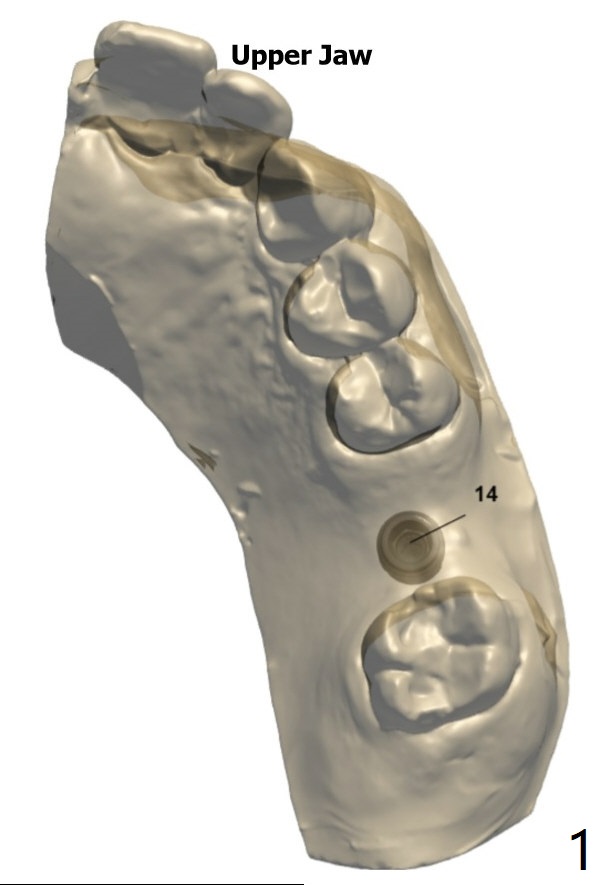

Implant Redo with Sinus Lift I

Return to No Deviation

Xin Wei, DDS, PhD, MS 1st edition 02/21/2020, last revision 06/05/2020